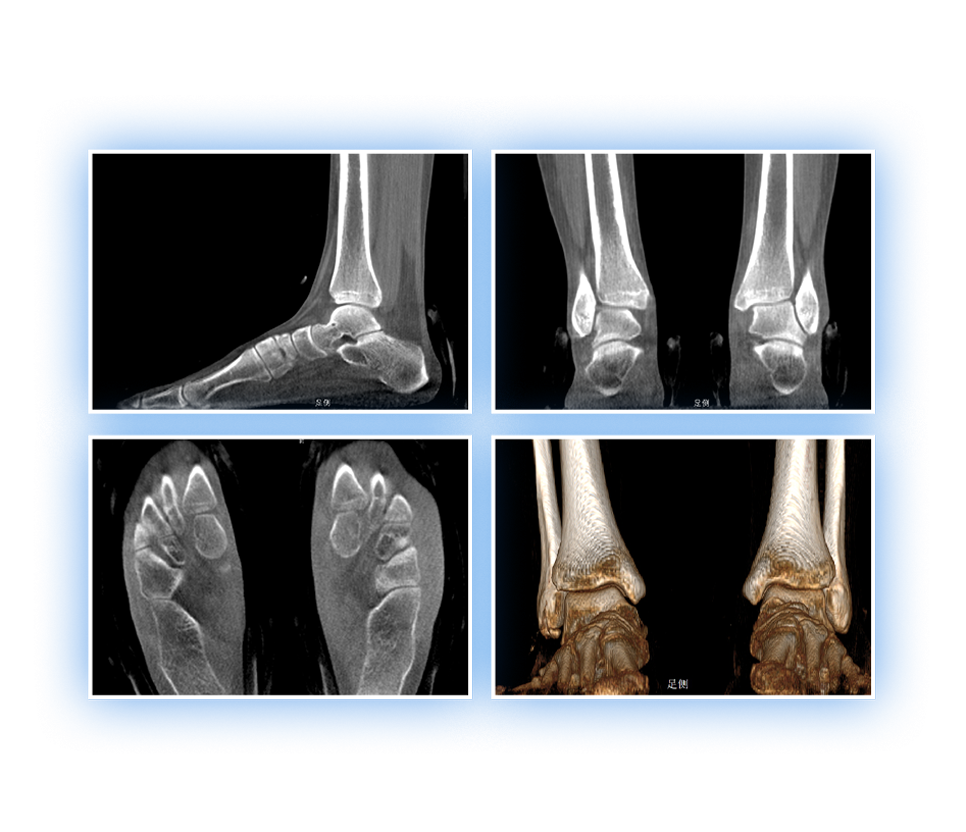

• 足踝

2D+3D一站式快速檢查